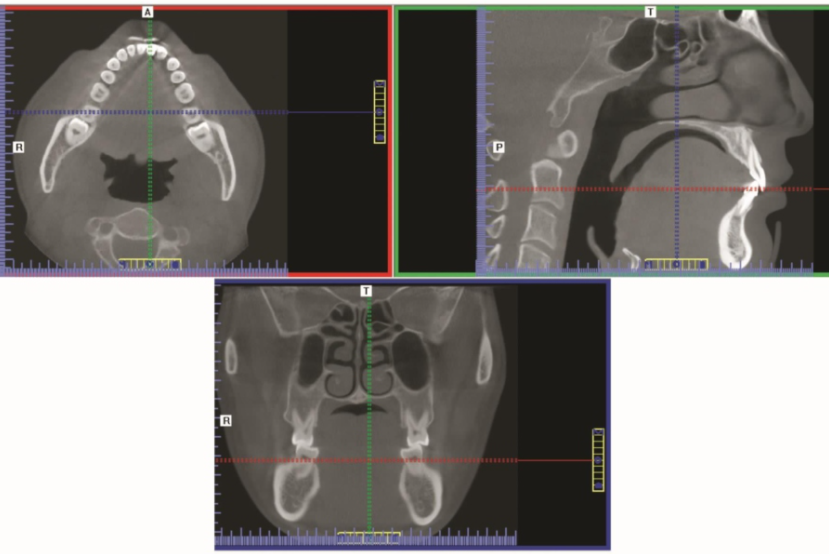

图3正常下颌骨CBCT平扫图像(经前牙区)CBCT三轴联动图像,显示x、y、z三个方向图像在不同层面的变化。

可以任意移动不同颜色的线,从而引起相应轴面图像的变化